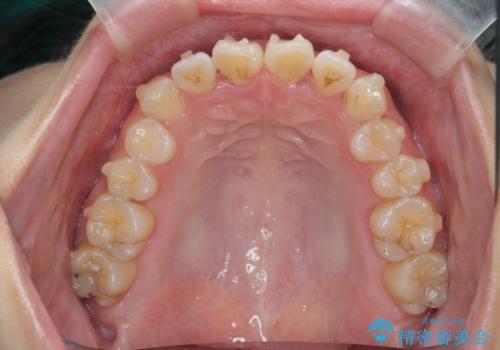

- 前歯のねじれを改善したい、と矯正治療を希望され来院されました。

上下の歯のがたつきを改善するマウスピース矯正治療と、下顎に見られる大きな骨隆起を外科的に除去する治療計画を進めていきます。

歯並びが改善したとともに、骨隆起を除去したことで舌をしまうスペースも増え安定した口腔内環境を確立することができました。